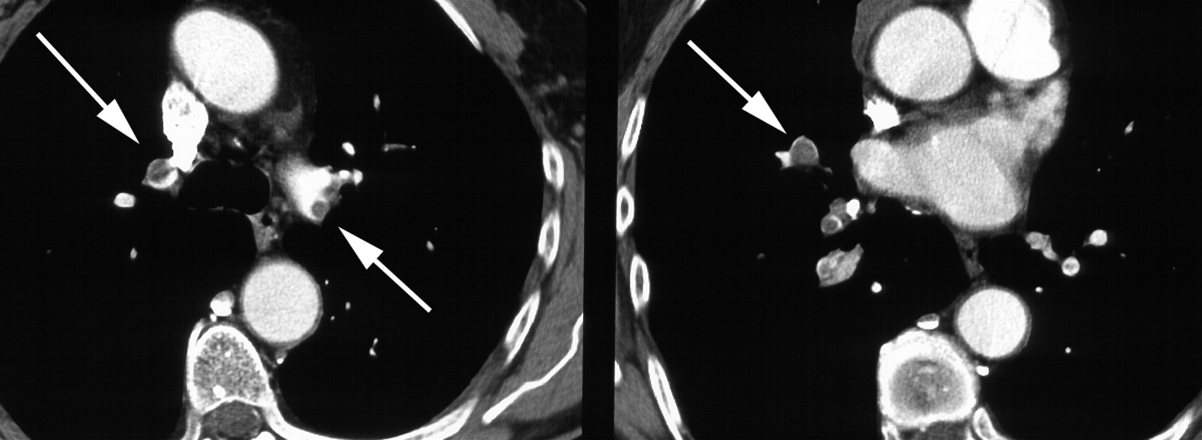

To CT-snit efter intravenøs kontrastinjektion viser embolier (mørke) omsluttet af kontrast-tilblandet blod (lyst) i over- og underlapsarterier bilateralt (pile).